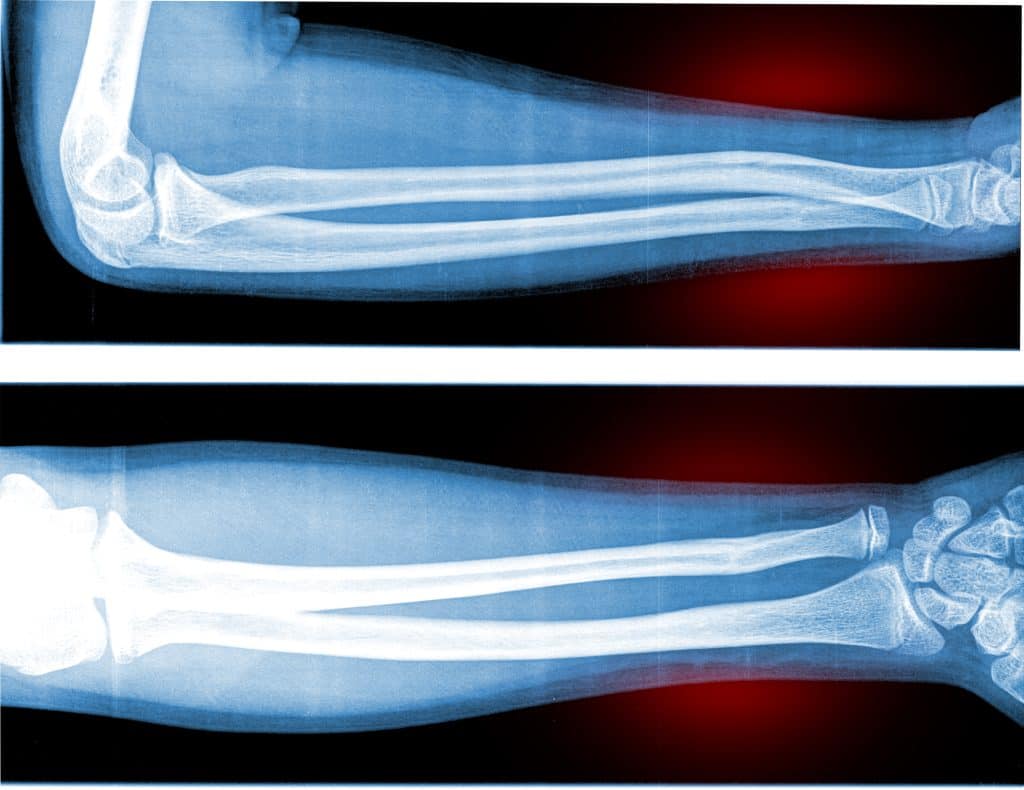

Duge kosti su najčešće na udaru prijeloma. Prijelomi se događaju onda kada dođe do izravnog udara na tvrdu površinu ili kada se zaprimi udarac tvrdim predmetom i kada se sila primjeni okomito na glavnu os same kosti. Prema karakteristikama, sami prijelomi dijafize mogu se svrstati u: Jednostavne oblike - onda kada se dijafiza prijelomi samo na jednoj točki. Složene oblike - kada se fraktura pojavi na dvije ili više mogućih točaka. Usitnjene oblike - dijafiza se lomi u više manjih fragmenata. Osim navedenog, frakture se mogu pojaviti i u: Poprečnim linijama - kada lom ima okomit pravac prema glavnoj osi kosti.

Kosa fraktura - kada je crta samog loma između 30 i 60 stupnjeva u odnosu sa samu glavnu os kosti. Spiralna fraktura - Nastaje spiralno puknuće oko kosti. Ovisno o samoj vrsti prijeloma odlučuje se vrsta liječenja i daljnje terapije. Liječenje se odvija prema dvije mogućnosti: Ortopedski oblik ili kirurško liječenje. Ortopedski oblik liječenja se odnosi na imobilizaciju limba i preko područja se stavlja ortopedsko pomagalo. Kirurško liječenje prijeloma uključuje operativni zahvat i ono je najčešće kod spiralnih fraktura koje su sitne i složene.